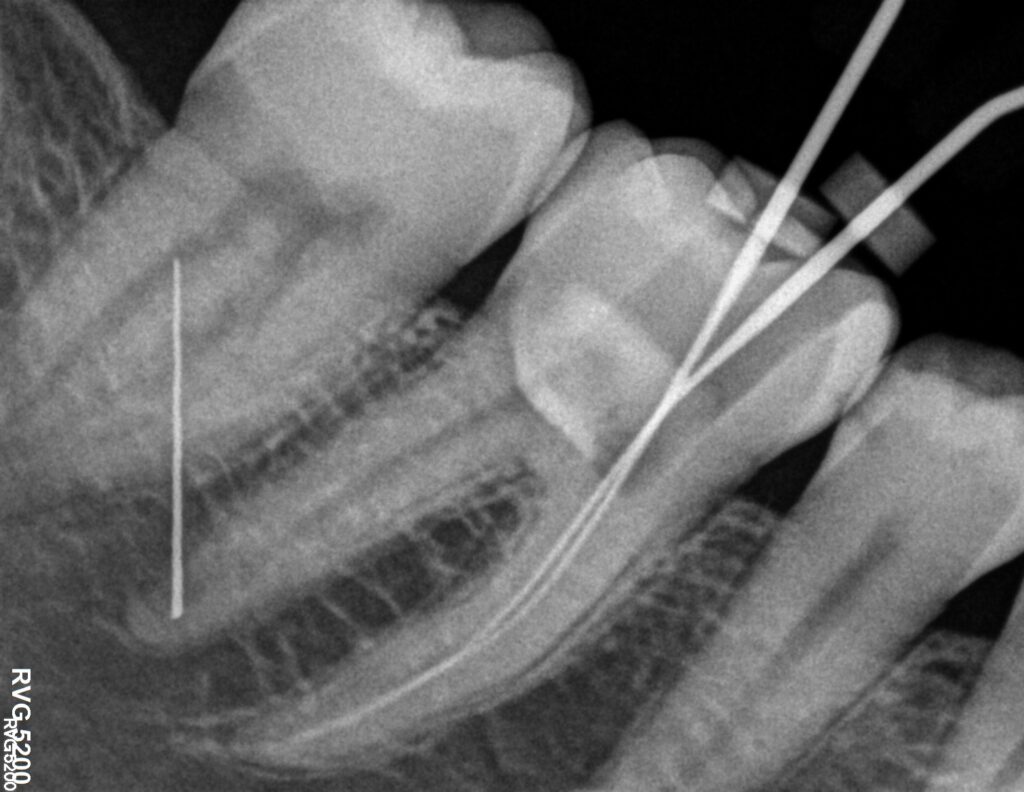

La Endodoncia es la rama de la odontología que se encarga del tratamiento de las patologías que afectan a los tejidos pulpares de los dientes como caries profundas, infecciones radiculares o fracturas.

Gracias a la endodoncia o tratamiento de conductos podemos conservar los dientes y su función. Cuando se deja que la caries dental evolucione o cuando el diente recibe un traumatismo importante éste termina afectando a los conductos donde está la pulpa dental (conocida como “nervio”). La acción de los microorganismos suele ser responsable de la infección e inflamación de la pulpa cuyo síntoma principal es el dolor agudo aunque a veces pueda pasar desapercibida. La evolución de esta inflamación termina en la “necrosis” o muerte de ésta, lo cual puede producir una infección o absceso a nivel óseo (flemón).

La Endodoncia limpia y conforma el interior de los conductos de las raíces dentales, sellándolos posteriormente impidiendo así la presencia de microorganismos en ellos. De este modo se consigue conservar el diente sin tener que extraerlo y la recuperación, en la mayoría de los casos, de la infección a nivel óseo.